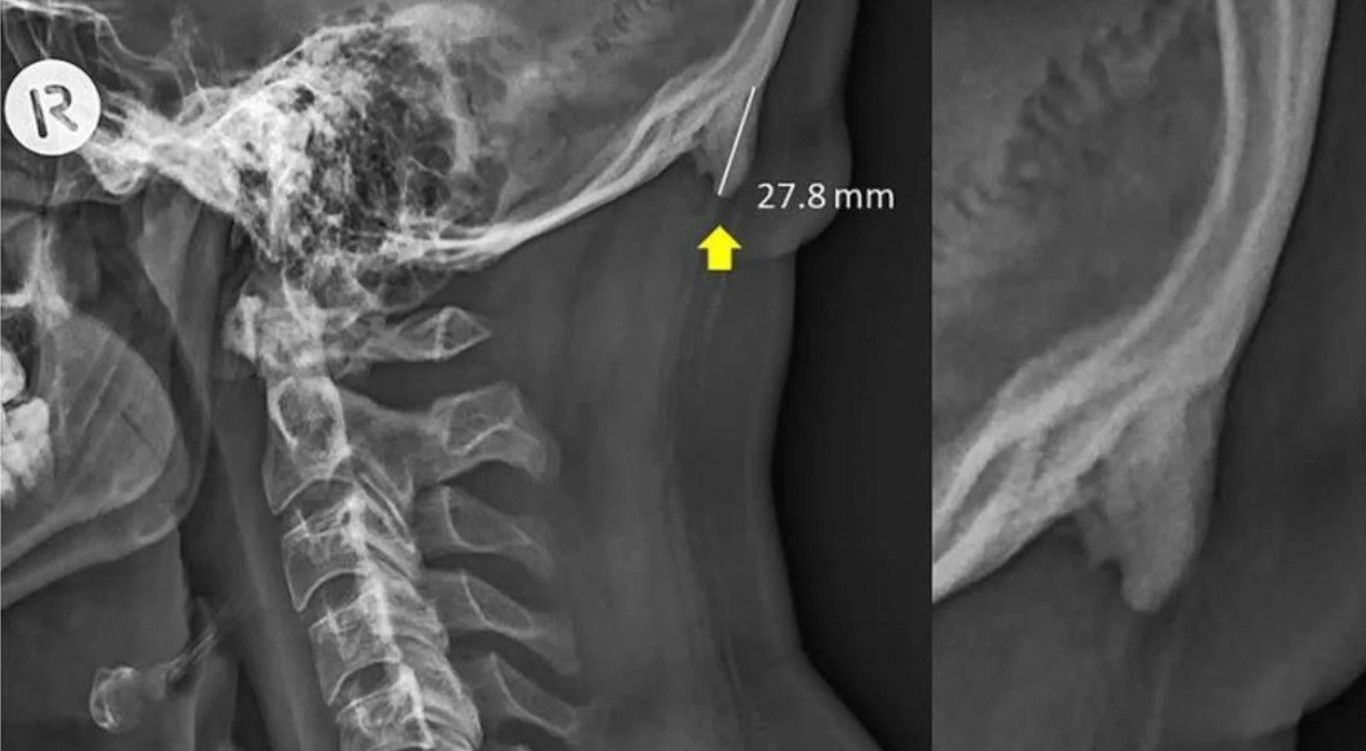

Qué es eso del cuerno en la cabeza: técnicamente una “protuberancia occipital externa” que se localiza justo en el punto entre el ligamento nucal y el trapecio. Las imágenes constatan ese pequeño cuernito en la nuca, que serviría como contrapeso craneal para el esfuerzo que hacemos bajando tanto la cabeza. El 40% de las radiografías que analizaron mostraban esa protuberancia.